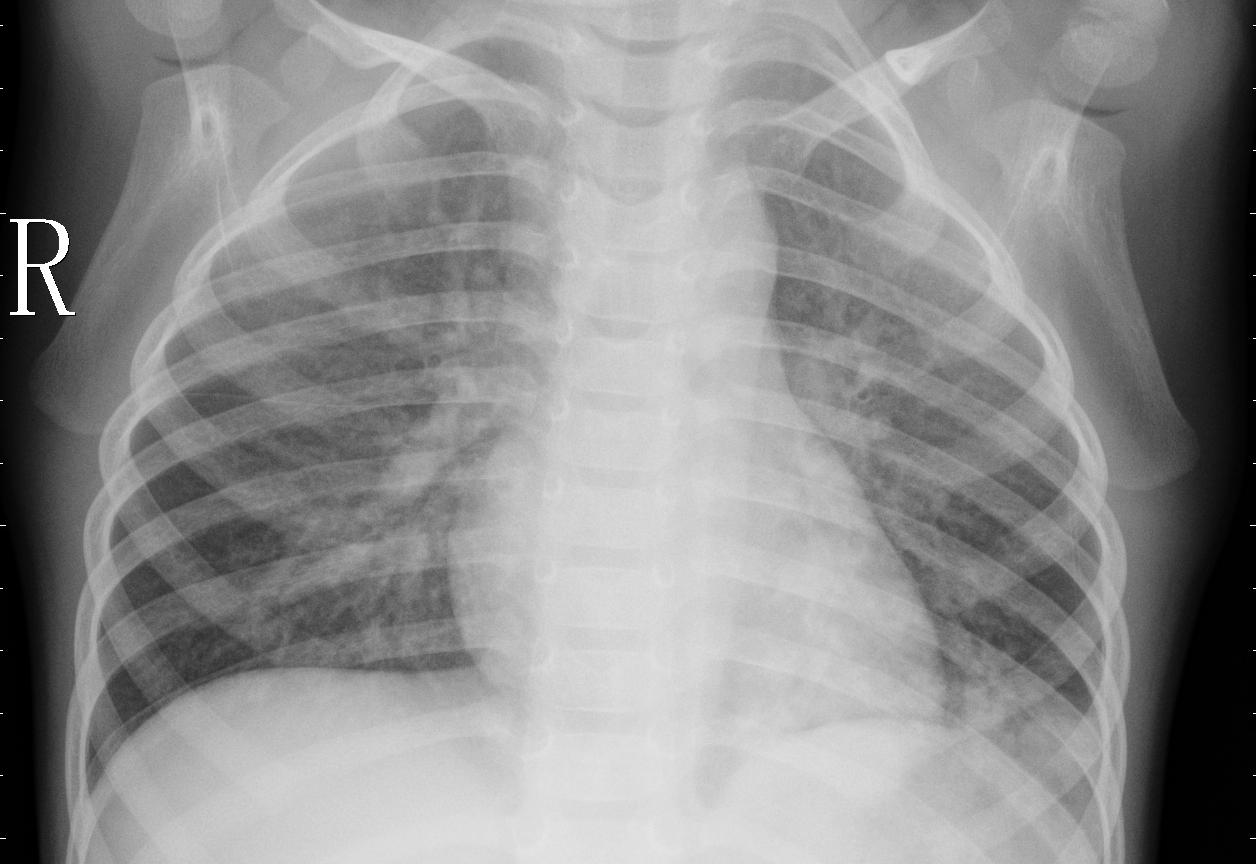

Papel da Radiografia de Tórax

A radiografia de tórax é um dos exames mais utilizados na investigação de pneumonia. Ela é relativamente barata, rápida e amplamente disponível, permitindo ao médico observar alterações pulmonares sugestivas da doença.

Sinais Radiográficos Clássicos da Pneumonia

De acordo com a literatura médica, alguns dos sinais mais comuns que um radiologista ou médico observa em uma radiografia de tórax são:

- Opacidades pulmonares: áreas esbranquiçadas na imagem, indicando acúmulo de líquido, secreção ou células inflamatórias.

- Consolidação alveolar: aspecto homogêneo e denso em parte do pulmão, podendo ocupar um lobo ou segmento.

- Broncograma aéreo: visualização dos brônquios cheios de ar cercados por áreas de consolidação (um sinal bastante característico de pneumonia).

- Infiltrados intersticiais: padrões difusos e reticulados, mais comuns em pneumonias virais ou atípicas.

- Assimetria pulmonar: quando um pulmão apresenta alteração evidente em comparação ao outro.

- Derrame pleural associado: em alguns casos, pode haver acúmulo de líquido na pleura, visível como apagamento dos ângulos costofrênicos.

Esses sinais devem ser interpretados em conjunto com o quadro clínico do paciente (tosse, febre, falta de ar, dor torácica), já que alterações semelhantes podem ocorrer em outras doenças (ex.: tuberculose, insuficiência cardíaca, atelectasia).

A radiografia de tórax é um dos exames mais solicitados no mundo para avaliação de doenças pulmonares. Dentre elas, a pneumonia se destaca como uma das mais graves e comuns, exigindo diagnóstico rápido e preciso.

Com o avanço da Inteligência Artificial, especialmente das redes neurais convolucionais (CNNs), tornou-se possível treinar modelos capazes de identificar padrões radiológicos sutis com alto grau de acerto.

Este projeto demonstra como um modelo de IA pode ser aplicado ao diagnóstico automático de pneumonia a partir de imagens de raio-X, utilizando redes neurais profundas e explicabilidade visual (Grad-CAM).